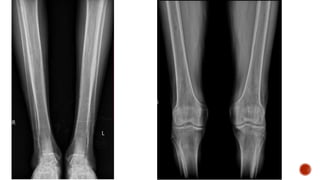

 AP and lateral radiographs of the skull show multiple tiny lucent areas with areas of

sclerosis in between, giving rise to salt and pepper skull appearance.

 Radiographs of both the legs, knees and left humerus show diffuse osteoporosis with

few well defined lytic areas.